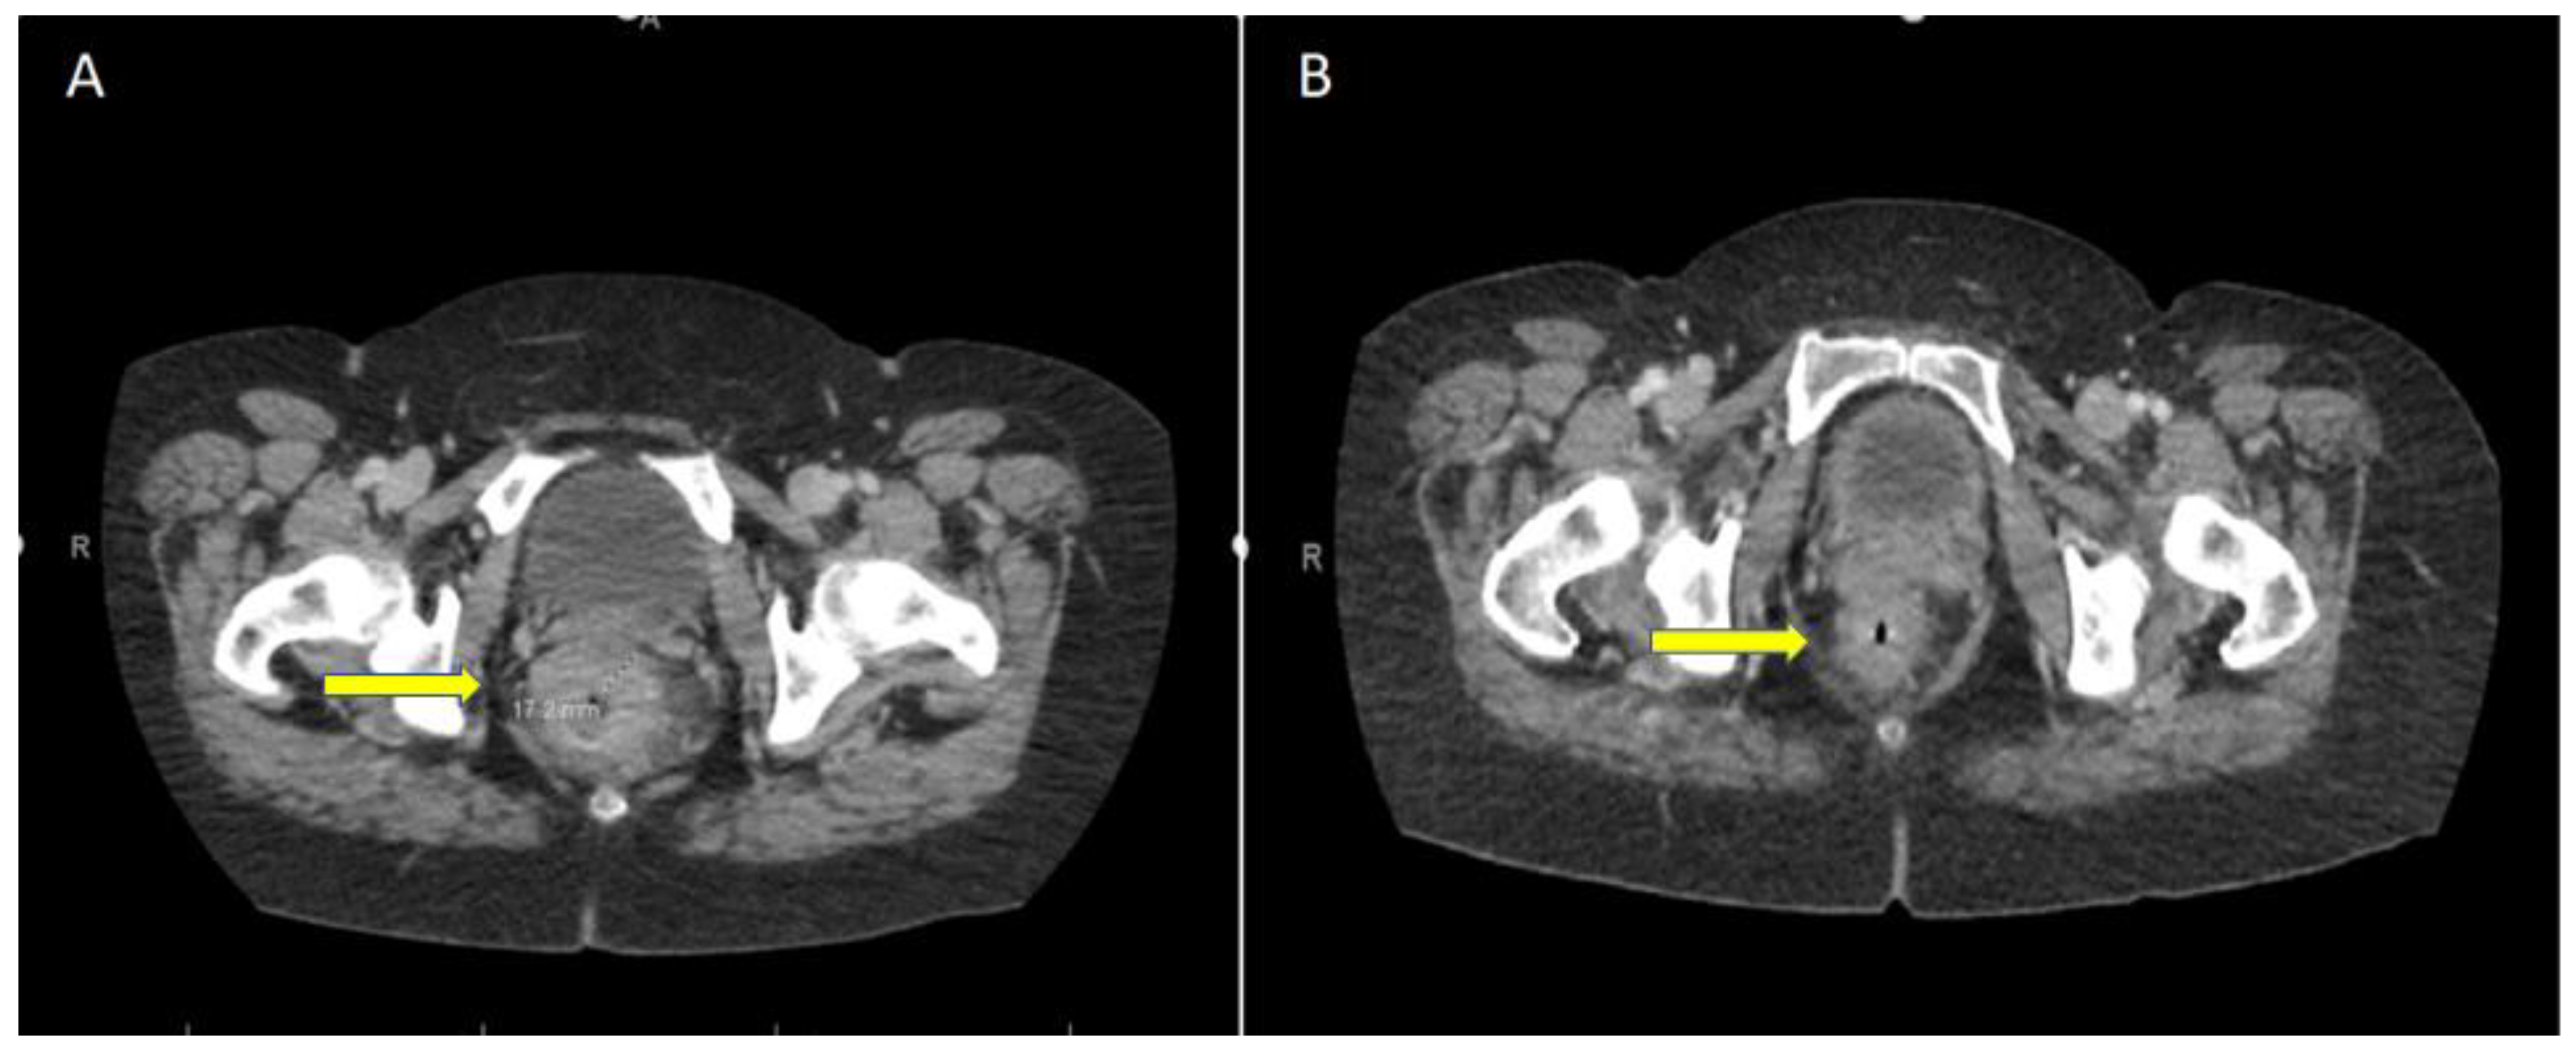

4. Current Management of dMMR Rectal Cancer

5. Case Report: ICI with Total Remission in dMMR laRC after a Single Cycle

6. ICI Toxicity Management

7. Response Assessment and Management of Immunotherapy-Related Rectal Stricture